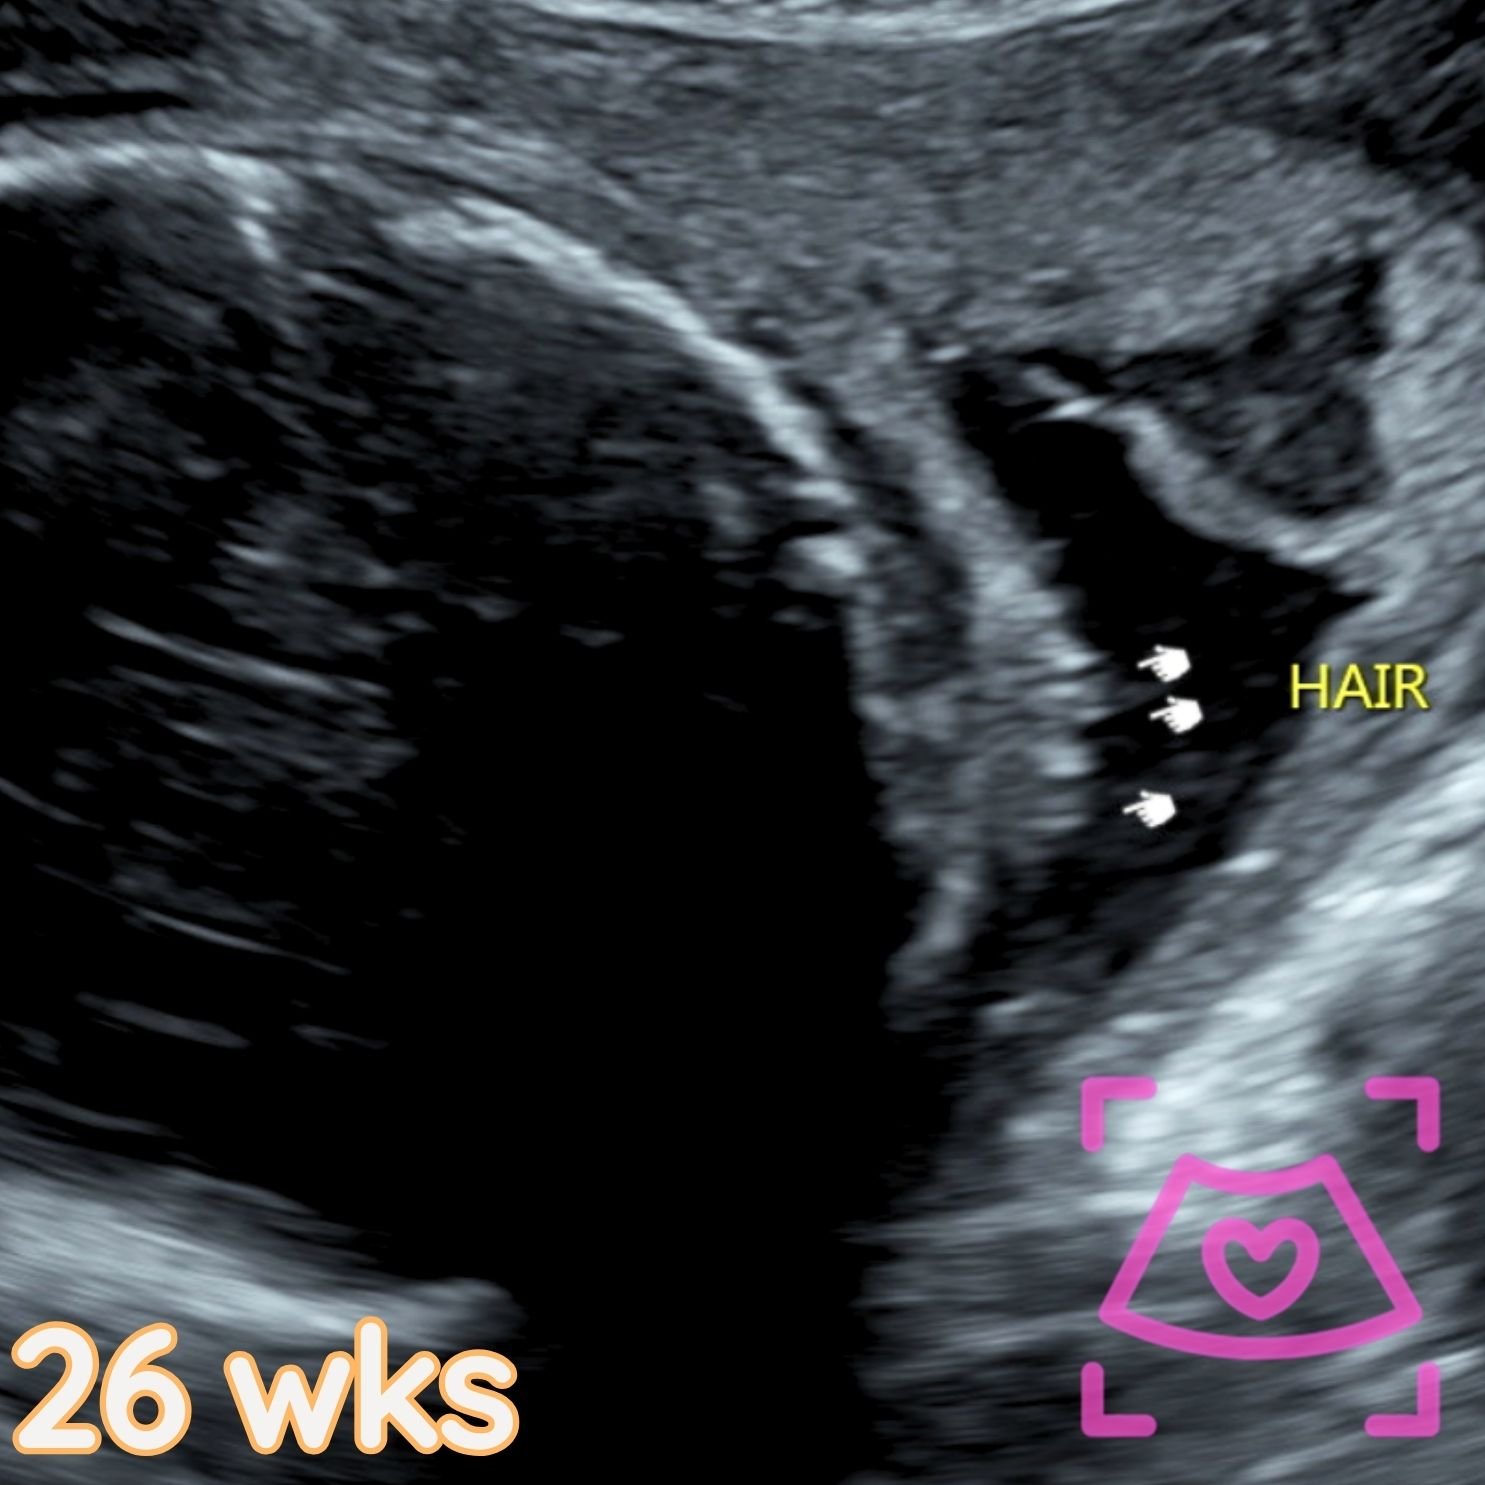

All ultrasounds at this facility are performed abdominally (on top). See examples below from 5-40 weeks! Recommended times can be found on the Services Page and when booking.

2nd Trimester